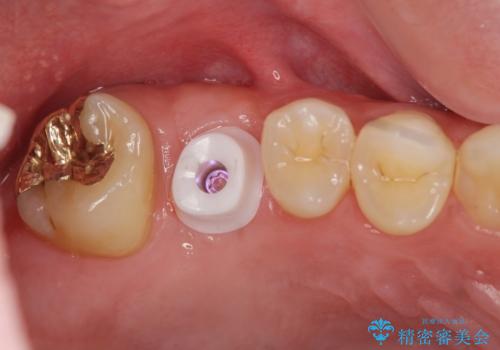

ソケットリフトを伴うインプラント補綴

骨量が不十分であった為、ソケットリフトを併用しインプラントによる補綴計画を立てます。

上顎のインプラントは、上顎洞底までの距離が短い場合ソケットリフト法を行い骨量を増やしたのちにインプラント埋入を行うことでより長期的な予後を見込むことができます。